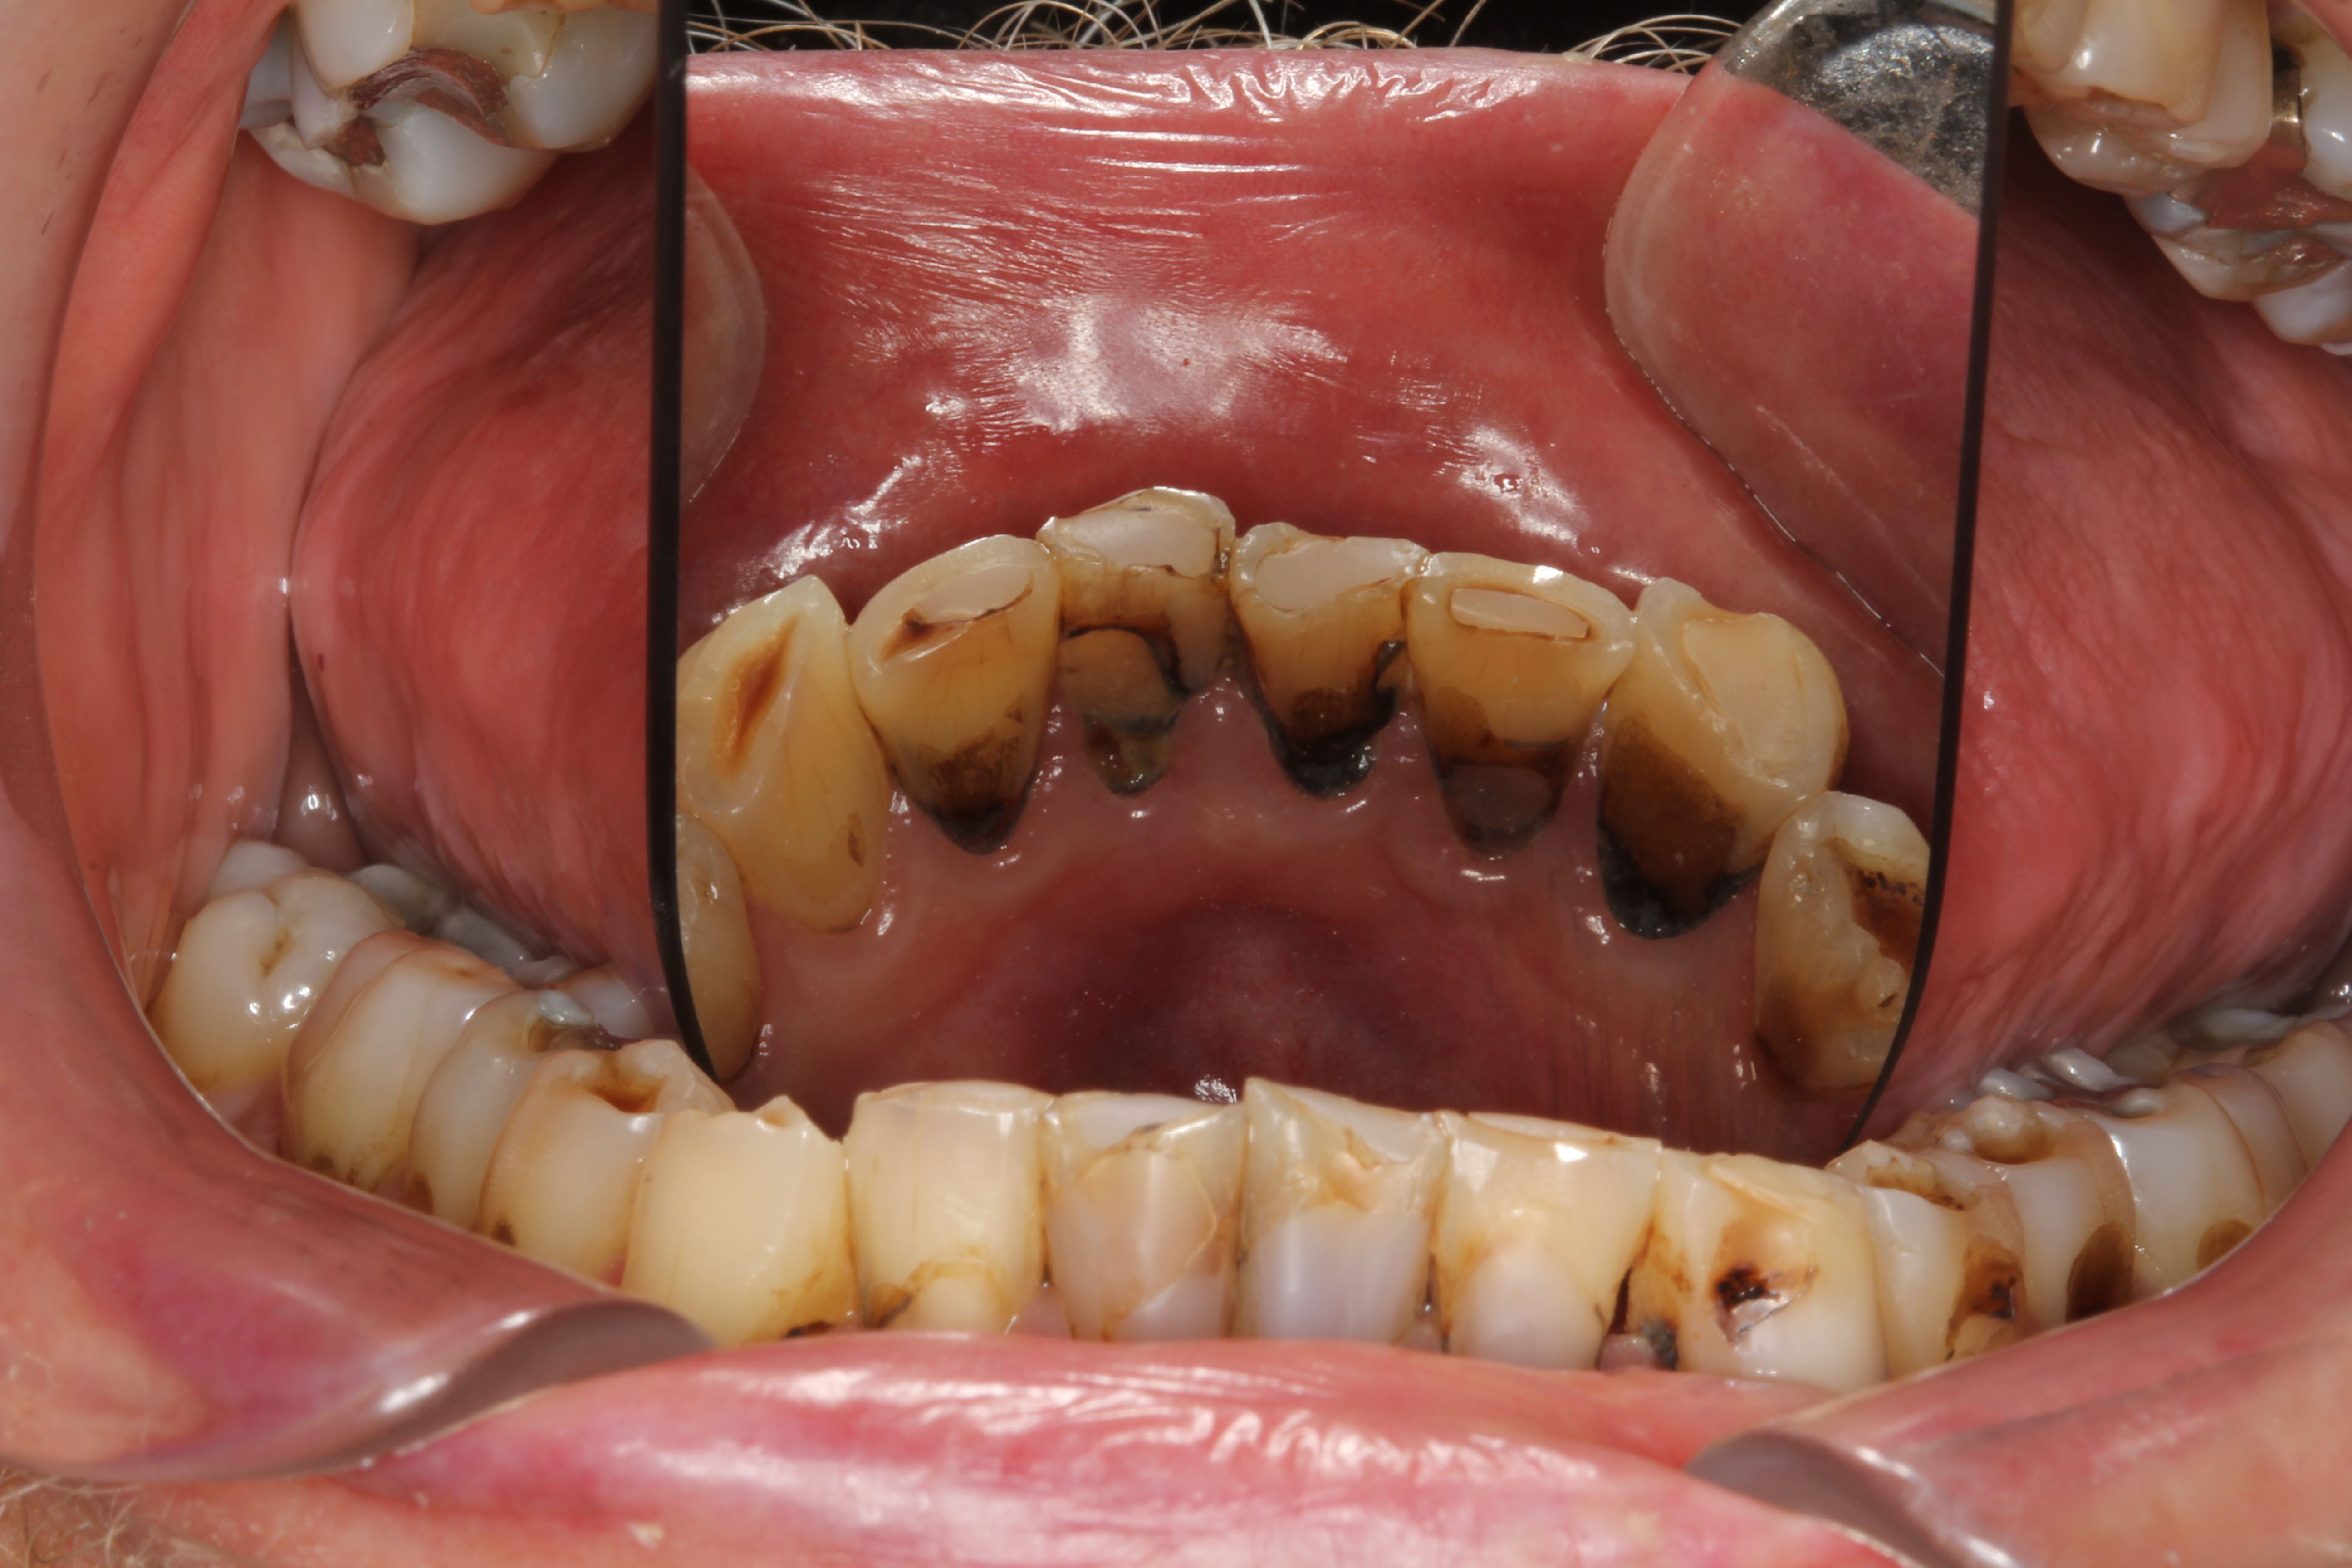

(2.) Lingual and facial maxillary views of 5-year-old patient, 1 year after caries attenuation with SDF. The parents were not concerned about the black staining.

Figure 2

(3.) Lingual and facial maxillary views of 5-year-old patient, 1 year after caries attenuation with SDF. The parents were not concerned about the black staining.

Figure 3